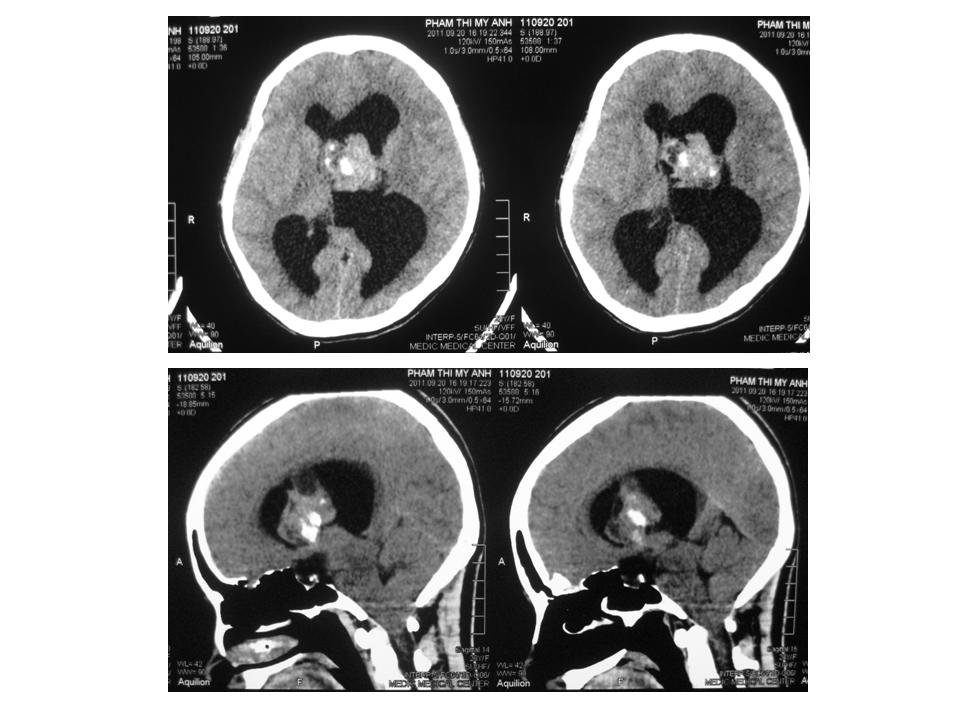

Siêu âm mắt nghĩ đến tăng áp lực nội sọ, đề xuất chụp MDCT não tìm nguyên nhân tăng áp nội sọ. Trên phim MDCT, thấy 1 u từ đám rối màng mạch não thất bên, có vôi hóa, khoảng 30mm, gần lỗ Monro và giãn não thất bên bên T nhiều hơn bên P.

Đây là một trường hợp tăng áp nội sọ mạn tính do u màng mạch não thất bên bên T chỉ có biểu hiện thực thể ở mắt (phù gai thị, tăng ONSD T > P, mất thị lực từng lúc). Vì bệnh nhân có u tuyến bã quanh mũi nên cần tìm thêm bằng chứng bệnh u xơ thần kinh (neurofibromatosis) Recklinghausen.